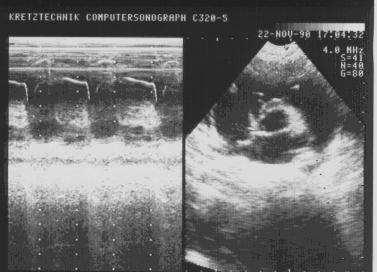

Исчезновение А-волны, легочная гипертензия.

Рис.44.

Исчезновение

А-волны, легочная

гипертензия.